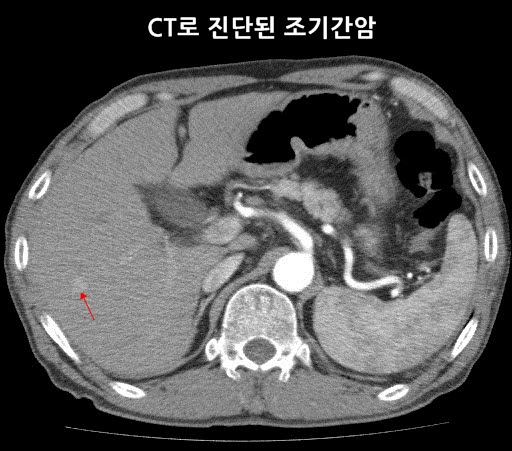

간은 인체에서 가장 큰 장기 중 하나로, 여러 가지 중요한 기능을 수행합니다. 간 질환은 매우 일반적인 문제로, 신속하고 정확한 진단이 필요합니다. 복부 CT를 통해 간의 경화, 종양, 지방간 등 다양한 문제를 확인할 수 있습니다. 특히 간암의 경우, CT 촬영은 초기 단계에서 종양의 크기와 위치를 평가하는 데 중요한 역할을 합니다. CT 이미지는 간 내 혈관과 주변 조직의 상태를 상세히 보여주기 때문에, 간암이 다른 장기로 전이되었는지 파악하는 데도 유용합니다.

간암: 조기 진단의 중요성

간암은 조기 증상이 거의 없기 때문에 진단이 늦어지는 경우가 많습니다. 그러나 복부 CT를 통해 초기 증상을 발견할 수 있다면, 치료 옵션이 훨씬 다양해집니다. 간암의 원인으로는 간염 바이러스 감염, 알코올 남용, 비만 등이 있으며, 이들 요인을 관리함으로써 예방할 수 있습니다. CT 촬영을 통해 조기에 간암을 발견하면, 간 절제술이나 간 이식과 같은 치료를 통해 생존율을 높일 수 있습니다.